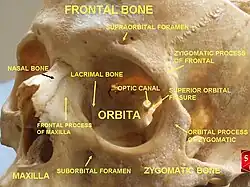

Fossa infratemporal esquerda. O crânio da frente.

O crânio da frente. Seção horizontal das cavidades nasais e orbitárias.

Óculos orbicular esquerdo, visto por trás. Ossos zigomáticos.

Ossos zigomáticos.